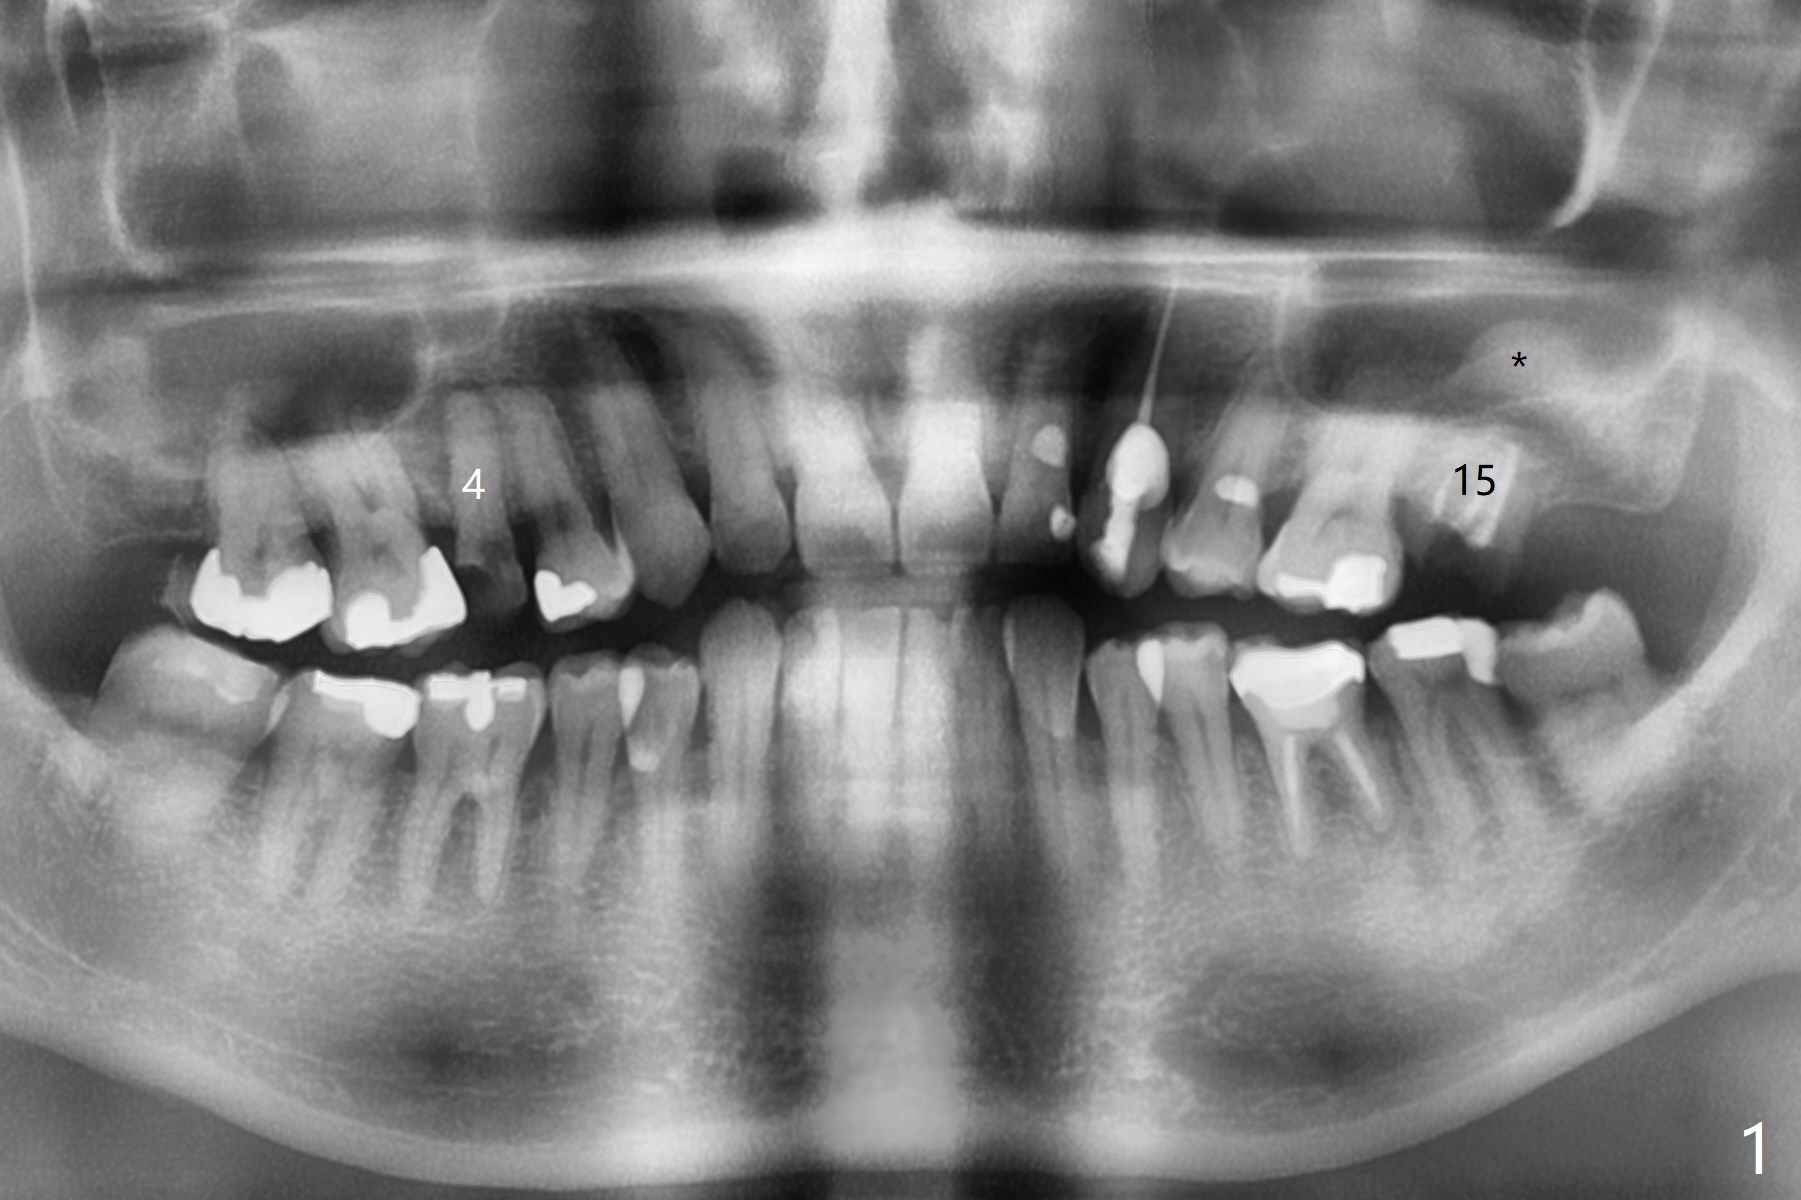

A 54-year-old man (smoker (3-4 cigarettes/day)) has two teeth that need to be replaced by implants (Fig.1). In order not to disturb the mucocele (Fig.1 *) above the tooth #15 to large degree, a short implant will be placed in the septum (not in the buccal socket (not disrupt the short buccal plate), Fig.2). Prepare PRFx1. Double check salvageability of the tooth #4. If needed, a 4.5x13 mm implant will be placed (Fig.3).